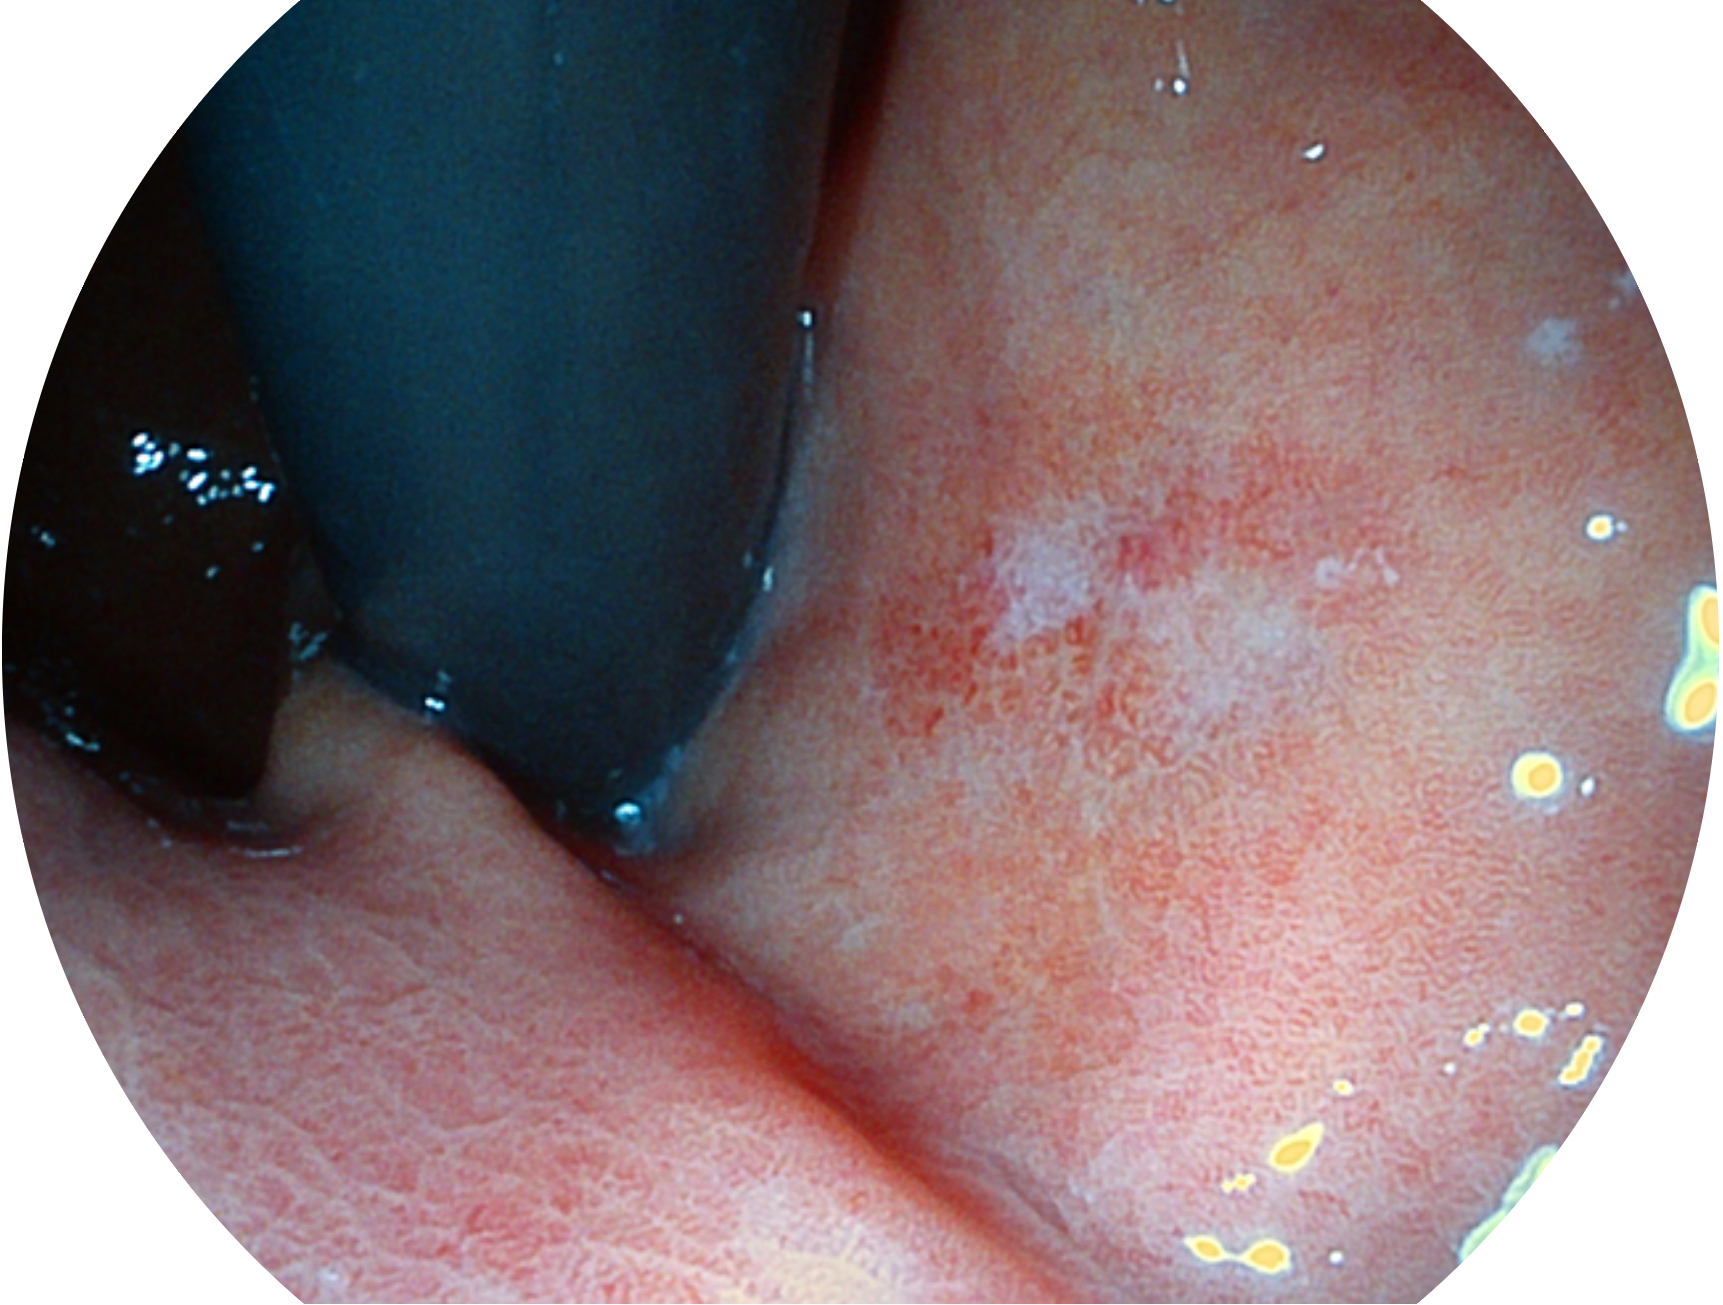

開立新開發(fā)的內(nèi)鏡染色技術(shù),主要是基于多波長LED 光源的開發(fā),VLS-55Q 四波長LED 光源是由四個不同顏色的LED光按照相應(yīng)照明模式所規(guī)定的特定發(fā)光比例進(jìn)行合束后形成,合束后形成的照明光的光譜由紅光、綠光、藍(lán)光及藍(lán)紫光這四個不同的波段范圍構(gòu)成。具有更高光譜自由度,通過光譜比例的控制,實現(xiàn)了聚譜成像技術(shù),英文全稱為“Spectral Focused Imaging, SFI”,縮寫為“SFI”和光電復(fù)合染色成像技術(shù),英文全稱為“Versatile Intelligent Staining Technology, VIST”,縮寫為“VIST”。